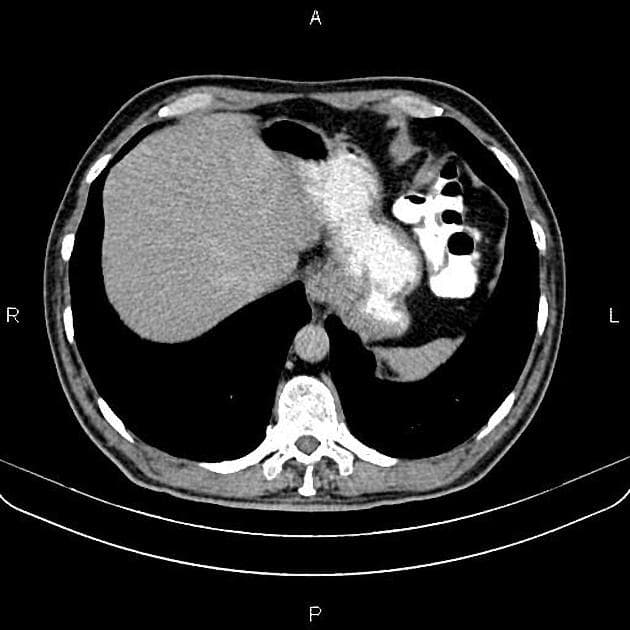

Axial C+ portal venous phase

- Cắt ngang CT qua thận cho thấy tổn thương giảm tỷ trọng ở thận trái, đặc điểm của mô mỡ, kèm theo tụ dịch quanh thận, nhiều khả năng là máu.

- Hình ảnh này phù hợp với u mạch cơ mỡ thận chảy máu (bleeding angiomyolipoma).

- Không thấy bằng chứng của các tổn thương khác gây chảy máu khoảng sau phúc mạc.